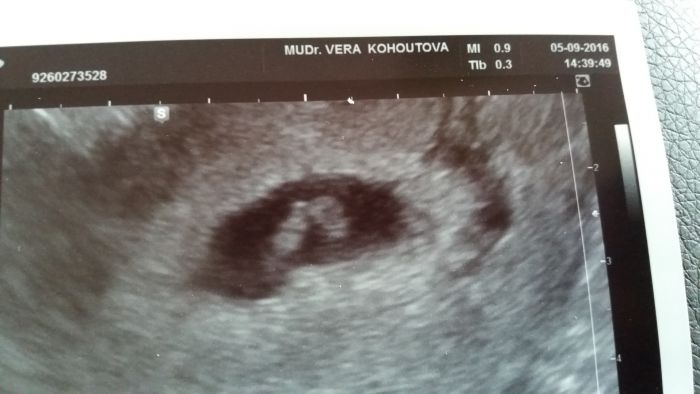

Dnes jsem byla u lékaře a mám koncene fotecku. Srdíčko uz krásně bouchalo a je vše v pořádku na další uz jdu za 14 dní.

Doktorka me hlídá, protože jsme se o to snažili dlouho a před tím jasem mela zdravotní problémy. Doufám že vše je za mnou.

[934304]ahojda Adulajdo. Dvojčata to prý nejsou to více v pravo je zloudkovy vacek, ze kterého je vyživované a v levo je plod.